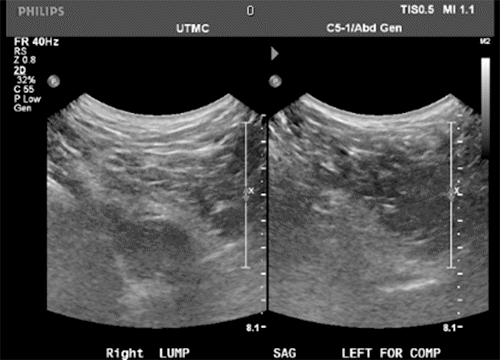

The patient is a 66-year-old White male with a medical history of morbid obesity who presented to the outpatient surgery clinic with swelling to the right gluteal area. He demonstrated a 10 × 12 cm soft tissue mass on physical examination along the right inferior gluteal fold. Though the lesion was clinically consistent with a lipoma, applying gentle pressure to the mass resulted in referred pain and pressure within the abdomen. There was no cough impulse, but movement was noticed in the abdomen when reducing the swelling. The differential diagnosis was expanded to include a soft tissue lesion extending from the pelvis and/or a hernia defect. Given the patient's habitus and equivocal physical exam findings, an ultrasound was performed, which noted a hypoechogenic area in the gluteal fold region appearing to herniate through a defect with coughing followed by spontaneous reduction. (Figure 1A) The contralateral region was imaged without similar findings, raising the suspicion of a gluteal hernia versus a gluteal lipoma. Due to poor compliance, the patient was initially lost to follow-up but returned to the clinic within a year with complaints of a symptomatic increase in the size of the swelling. A CT scan of the pelvis demonstrated a large well-circumscribed oval mass measuring 11.9 × 7.5 × 14.9 cm in the deep pelvis posterior and lateral to the rectosigmoid colon extending into the ischiorectal fossa on the right side. The internal density of the mass was 17 Hounsfield units. It appeared to be a cystic fluid collection with  possible blood or proteinaceous debris (Figure 1B and Figure 1C).

Figure 1. Ultrasound Imaging. Published with Permission

A) Hypoechogenic area in gluteal fold region, which appeared to herniate through defect with coughing and reduction.